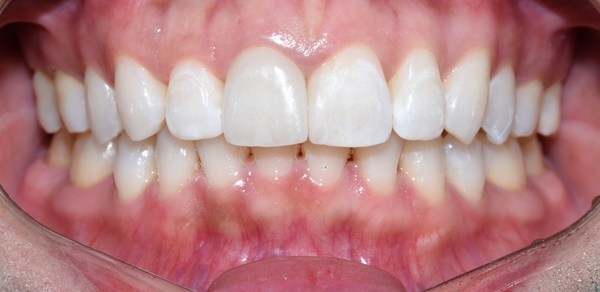

변화모습 다시 한번 처음 사진이랑 비교해 볼까요?

요렇게 티끌장치를 붙였고, 2주만에 이렇게 변화하셨습니다.

요렇게 마무리 되었습니다.

물론 안쪽에는 다시 틀어지지 않기 위해 유지장치 부착되어있습니다.